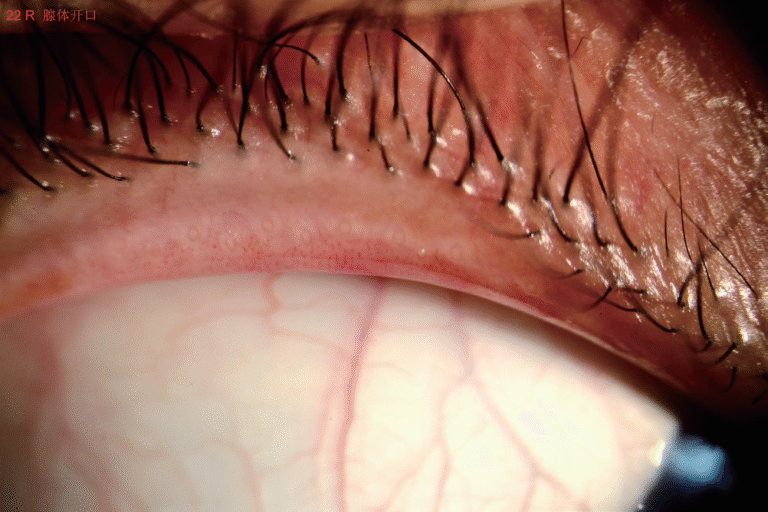

Dry Eye

Full ocular surface analysis

Advanced Dry Eye analysis

Built-in Digital Analysis